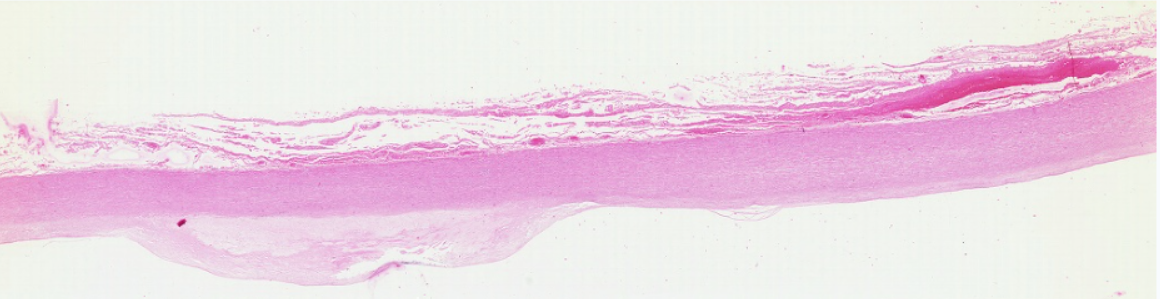

低倍镜结合高倍镜观察心壁分三层,由内向外观察:1. 心内膜:(1)内皮:较薄,表面为扁圆形的内皮细胞核。(2)内皮下层:其薄层结缔组织中含有少量平滑肌纤维。(3)心内膜下层:紧靠心肌膜为结缔组织,内含浦肯野纤维,其直径较一般心肌纤维粗,染色较浅,肌浆丰富,肌原纤维少,横纹不太明显。2. 心肌膜:最厚,占心壁的绝大部分,主要由心肌纤维组成,其间有结缔组织及丰富血管。3. 心外膜:为薄层结缔组织,富含毛细血管、神经及脂肪组织。其外表面被覆一层间皮。

1.全景图